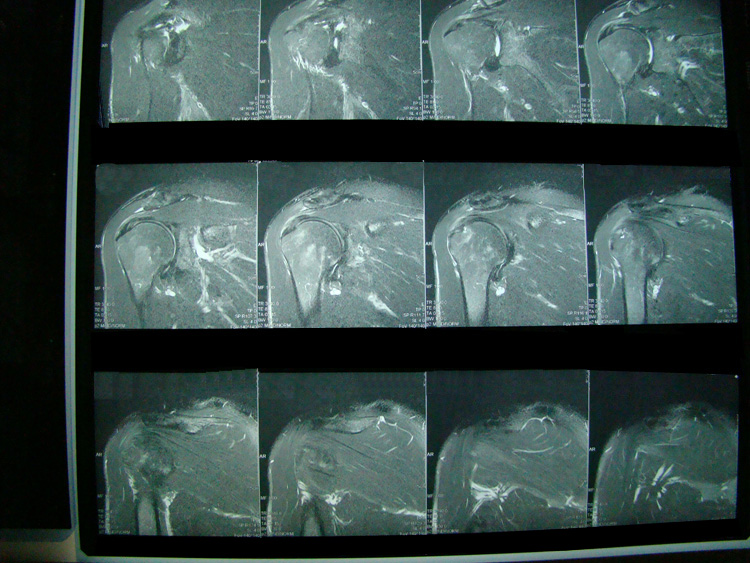

This patient presented with shoulder pain that interfered with work and exercise. The visible fluid-filled cysts on the “Before" MRIs are from chronically injured rotator cuff tendon roots.

The patient underwent treatments of a highly specialized fine-needling technique pioneered by Dr. Tallman.The follow-up MRI was done 2 months after his 6th treatment. He was released with a pain-free, full range of motion with unrestricted activities.